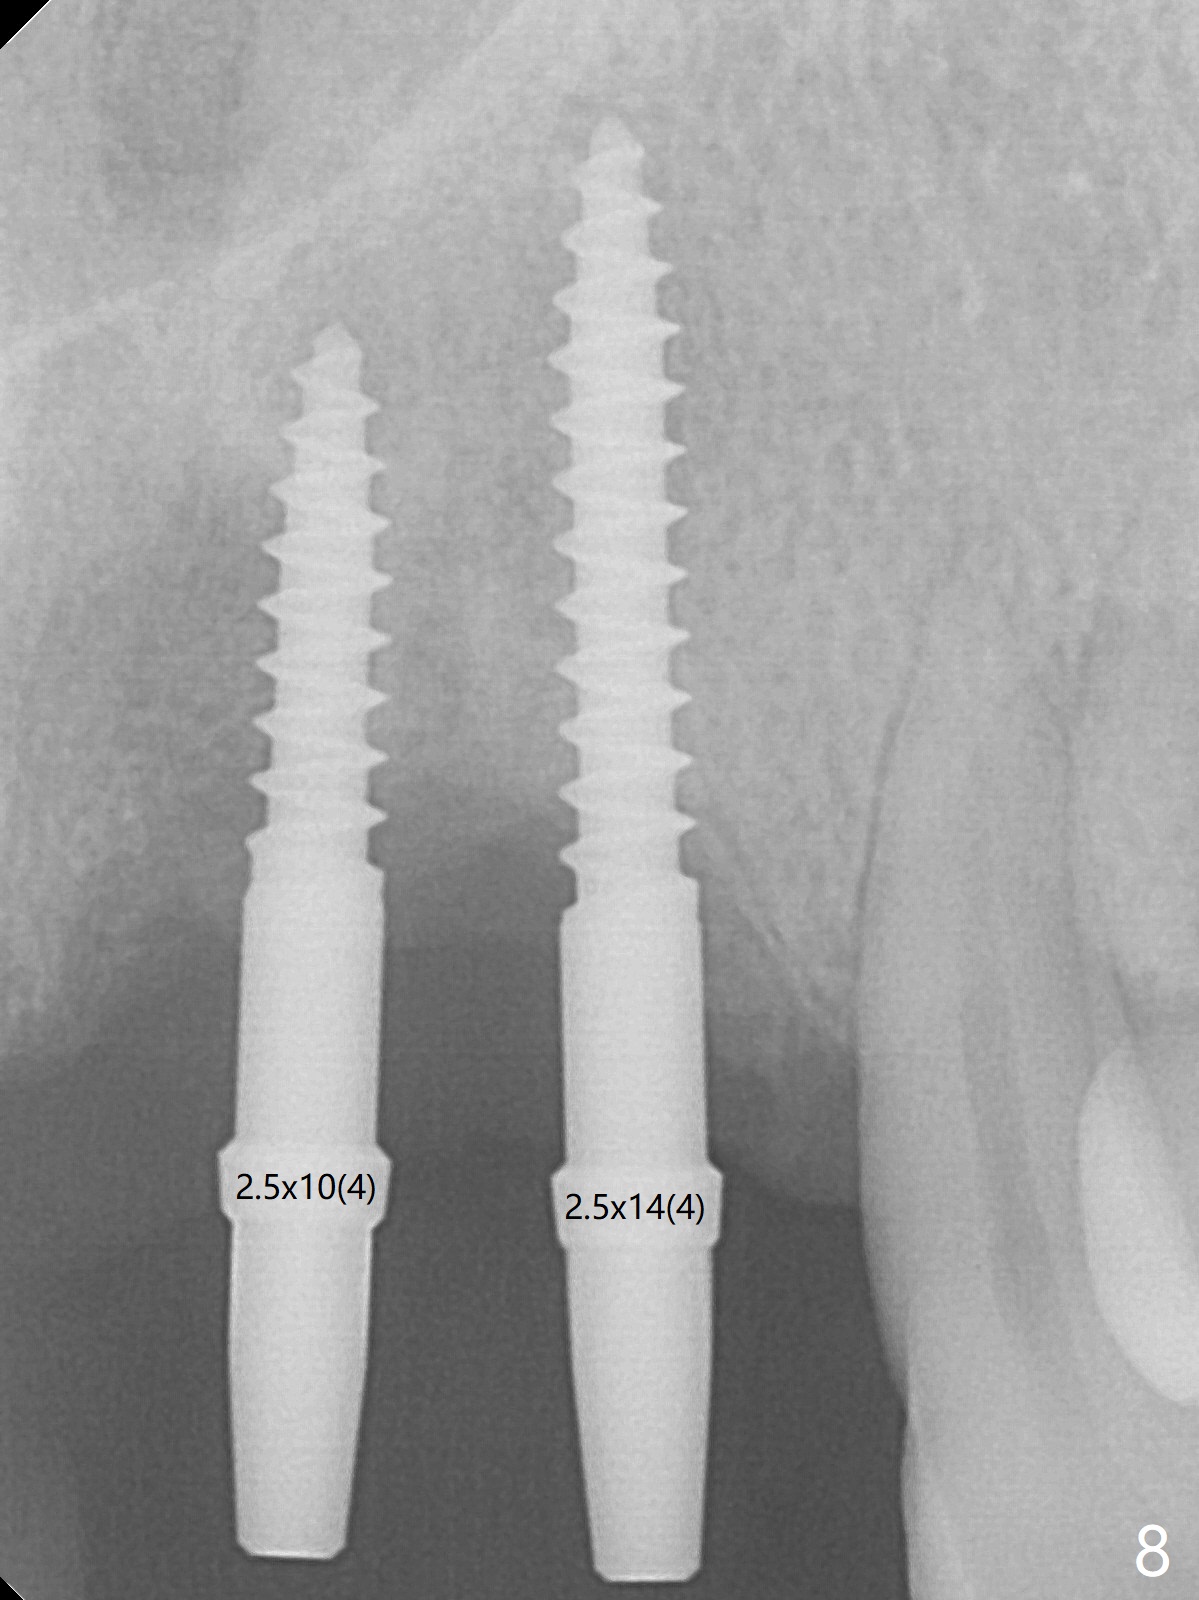

Although the ridge of the maxillary anterior ridge looks moderate in width (Fig.1), the bone is ~4 mm buccopalatally. Suction down surgical stent (Fig.2') made from the lab-fabricated provisional (Fig.2) will be used to check the position and trajectory of osteotomies. PAs taken after initial osteotomies (1.2 mm drill) show those at the central incisors tend to be mesial (close to the Incisive Canal *), while those at the lateral incisor sites distal (Fig.3,4). After adjustment, the position and trajectory of the osteotomies are acceptable (Fig.5,6). To reduce the chance of perforating the Incisive Canal (Fig.3,4 *), 2.5 mm 1-piece implants are inserted with >40 Ncm (Fig.7,8). After deep placement of the implants, Vanilla graft is placed at the crest (Fig.9,10 *). An immediate splinted provisional is fabricated from the suction down stent. The gingiva is healthy around the provisional (Fig.11) and the implants (Fig.12,13) 1 month postop. The provisional is adjusted monthly so that the interdental papillae can be elongated. No bone resorption is observed 6 months postop (Fig.14,15). Crowns are cemented 8 months postop (Fig.16-18). The keratinized gingiva appears to have formed the abutments 8 months postop immediately pre-cementation (Fig.19).